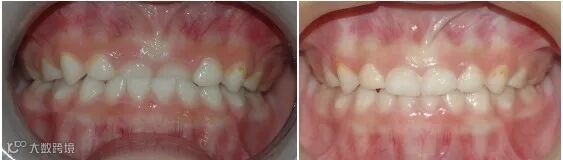

乳牙早失戴间隙保持器

门牙间隙过大(左侧图片为多生牙导致)